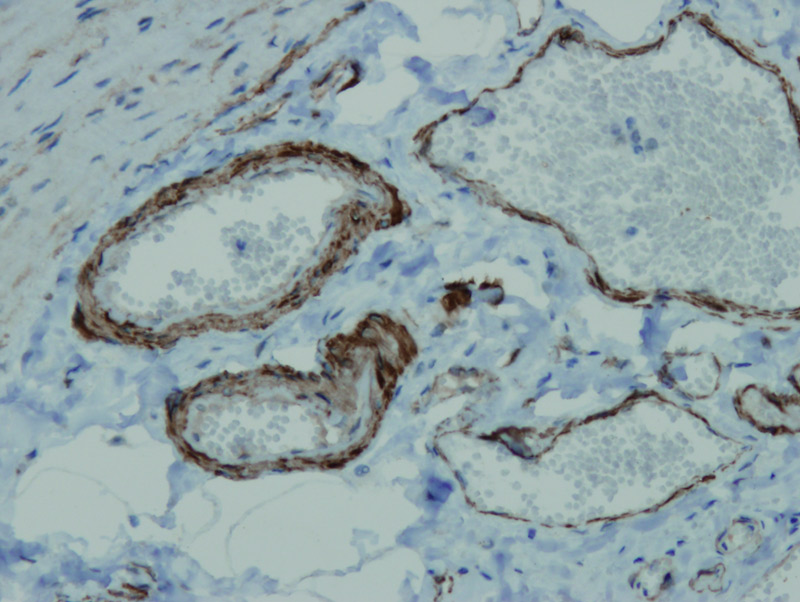

Anti-Alpha Smooth Muscle Actin

Peptid derivovaný z N-koncovej sekvencie ľudského alpha actin hladkého svalstva. Protilátka rozpoznáva epitop umiestnený medzi Glu3 - Gly16.

IHC-P, riedenie 1:100

db147